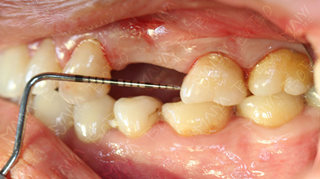

在麦芽口腔举办的公益活动中,赵女士成为首批公益种牙的幸运儿,麦芽口腔中方院长和麦芽特聘专家、人民医院口腔种植中心孙海鹏博士在对赵女士的牙齿情况做了综合检查深入分析指出,赵女士当前情况为左上4/5牙长期缺失,牙槽骨已经出现一定程度的萎缩吸收,如果长期以往不仅牙槽骨吸收越来越严重,也会影响到邻牙的健康,增加后期修复的难度。从X光全景片上,还可以看到,由于长期单侧咀嚼食物,患者脸型已经出现轻微偏脸畸形,影响了面部美观。

医生为赵女士检查牙齿情况

由于赵女士长期牙缺失,牙槽骨已经出现萎缩吸收,导致两边邻牙倾斜,因此她的牙缺失间隙在动态变小,牙齿的间隙不够种植两颗牙的位置,但是种一颗牙又显得空间有点偏大,最终游勤波院长和孙海鹏博士经综合考虑,采用麦芽数字化生物种植技术,数字化精准导航种植,采取了种植一颗连冠修复的方式,只需一颗种植钉就可以达到修复两颗牙齿的目的,仅仅不到一个小时就帮赵女士种上了牙齿。